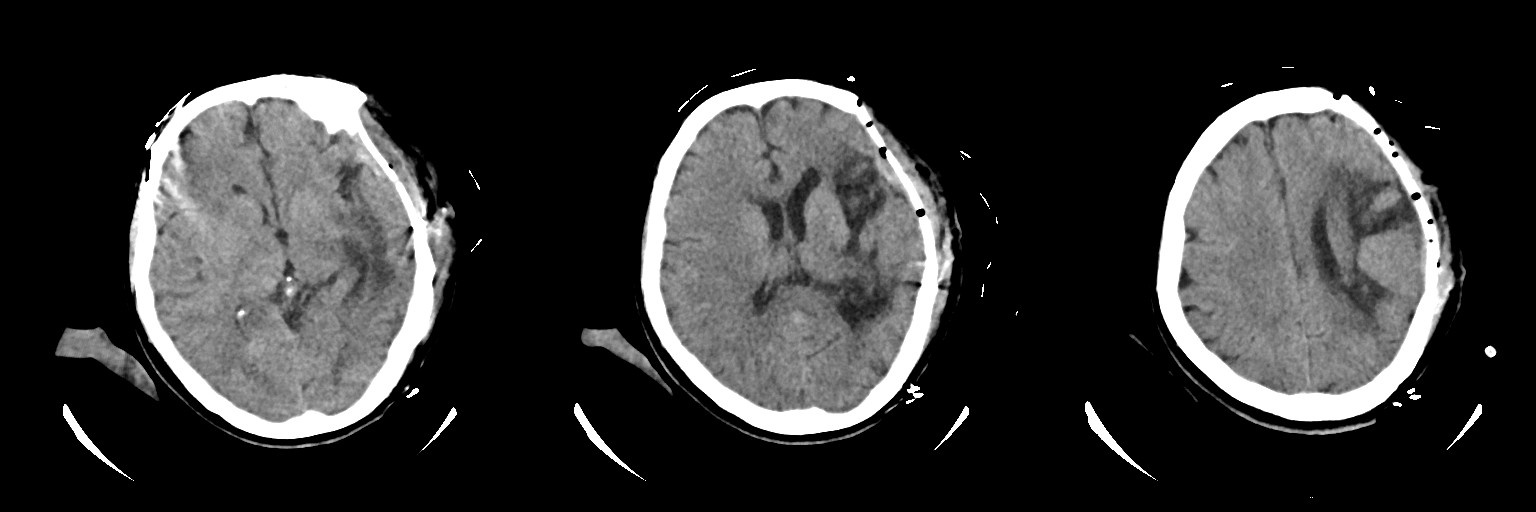

術后1天復查頭顱CT